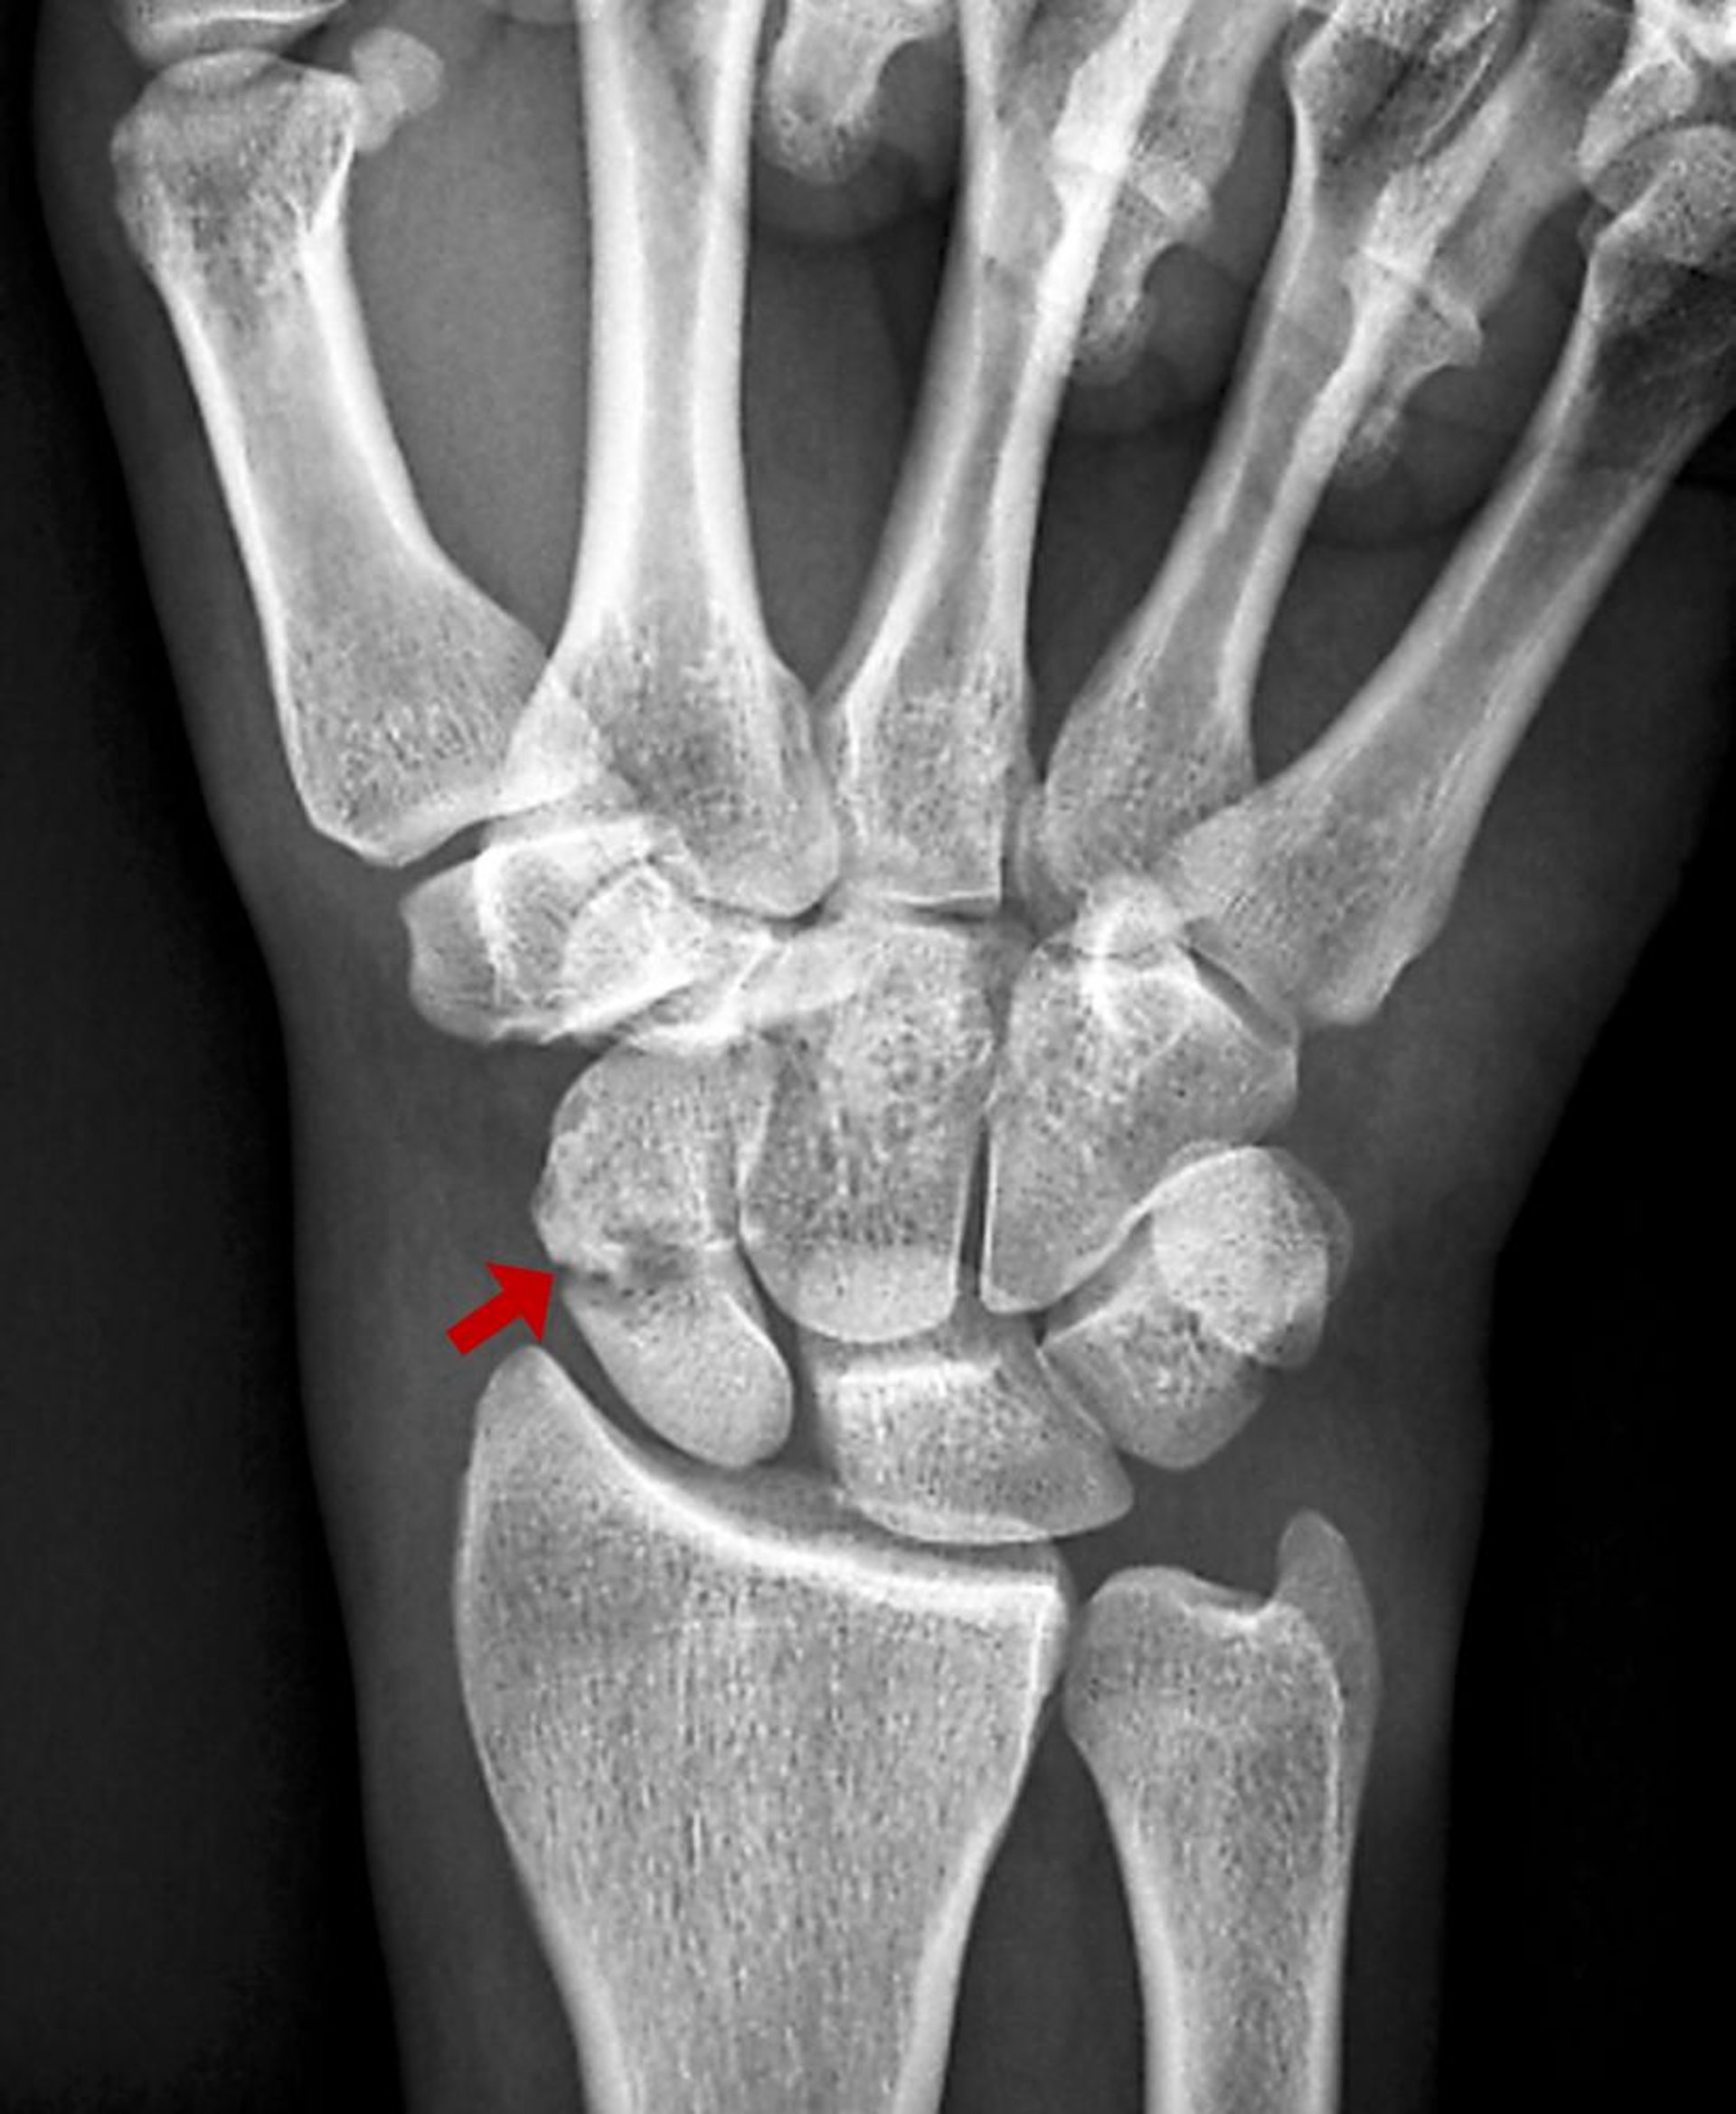

Cette fracture du scaphoïde est visible comme une zone radiotransparente sur la radiographie.

ZEPHYR/SCIENCE PHOTO LIBRARY